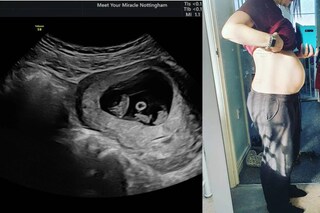

മേഗൻ സ്മിത്തും ക്ലേട്ടൺ വിറ്റേക്കറും അവരുടെ ആദ്യ ഡേറ്റ് നടത്തിയത് മെയ് മാസത്തിൽ ആയിരുന്നു. ജൂൺ മുതൽ ഇവർ ഒരുമിച്ചായി താമസം. ആദ്യത്തെ ലോക്ക് ഡൗൺ സമയത്ത് ഒരു ഡേറ്റിംഗ് ആപ്ലിക്കേഷനിൽ ആയിരുന്നു ഇവർ കണ്ടുമുട്ടിയത്. ഏതായാലും ഇപ്പോൾ തങ്ങളുടെ കടിഞ്ഞൂൽ കണ്മണികൾക്കായി കാത്തിരിക്കുകയാണ് ഇവർ. കഴിഞ്ഞ ദിവസം നടത്തിയ സ്കാനിംഗിൽ മൂന്ന് കുഞ്ഞുങ്ങളുണ്ടെന്ന റിപ്പോർട്ട് ഇരുവർക്കും വലിയ സന്തോഷമാണ് നൽകിയിരിക്കുന്നത്.

സ്വാഭാവിക ഗർഭധാരണത്തിലൂടെ 200 ദശലക്ഷം കേസുകളിൽ ഒന്നിൽ മാത്രമാണ് ഒരേ പൊലെയുള്ള മൂന്ന് കുഞ്ഞുങ്ങൾ(identical triplets) ജനിക്കാനുള്ള സാധ്യത. ഏതായാലും അടുത്ത ഏപ്രിൽ മാസം ആകുമ്പോഴേക്കും മേഗൻ സ്മിത്തിന്റെയും ക്ലേട്ടൺ വിറ്റേക്കറുടെയും ജീവിതത്തിൽ മൂന്ന് അതിഥികൾ കൂടിയെത്തും.

2013ൽ ഭർത്താവ് മരിച്ചുപോയ മേഗൻ ഈ വർഷം ജനുവരിയിൽ കാമുകനുമായി വേർപിരിയുകയും ചെയ്തിരുന്നു.പരസ്പരം കണ്ടുമുട്ടിയതിനു ശേഷം ഒരു ദിവസം പോലും ഒരുമിച്ചല്ലാതെ ചെലവഴിച്ചിട്ടില്ലെന്ന് മേഗൻ പറഞ്ഞു. സെപ്റ്റംബറിലാണ് മേഗൻ മൂന്ന് കുഞ്ഞുങ്ങളെ ഗർഭം ധരിച്ചിരിക്കുകയാണെന്ന് ഇവർ തിരിച്ചറിഞ്ഞത്. അതീവ സന്തോഷത്തിലാണെന്നും കുഞ്ഞുങ്ങൾക്കായി കാത്തിരിക്കുകയാണെന്നും ക്ലേട്ടൺ പറഞ്ഞു.